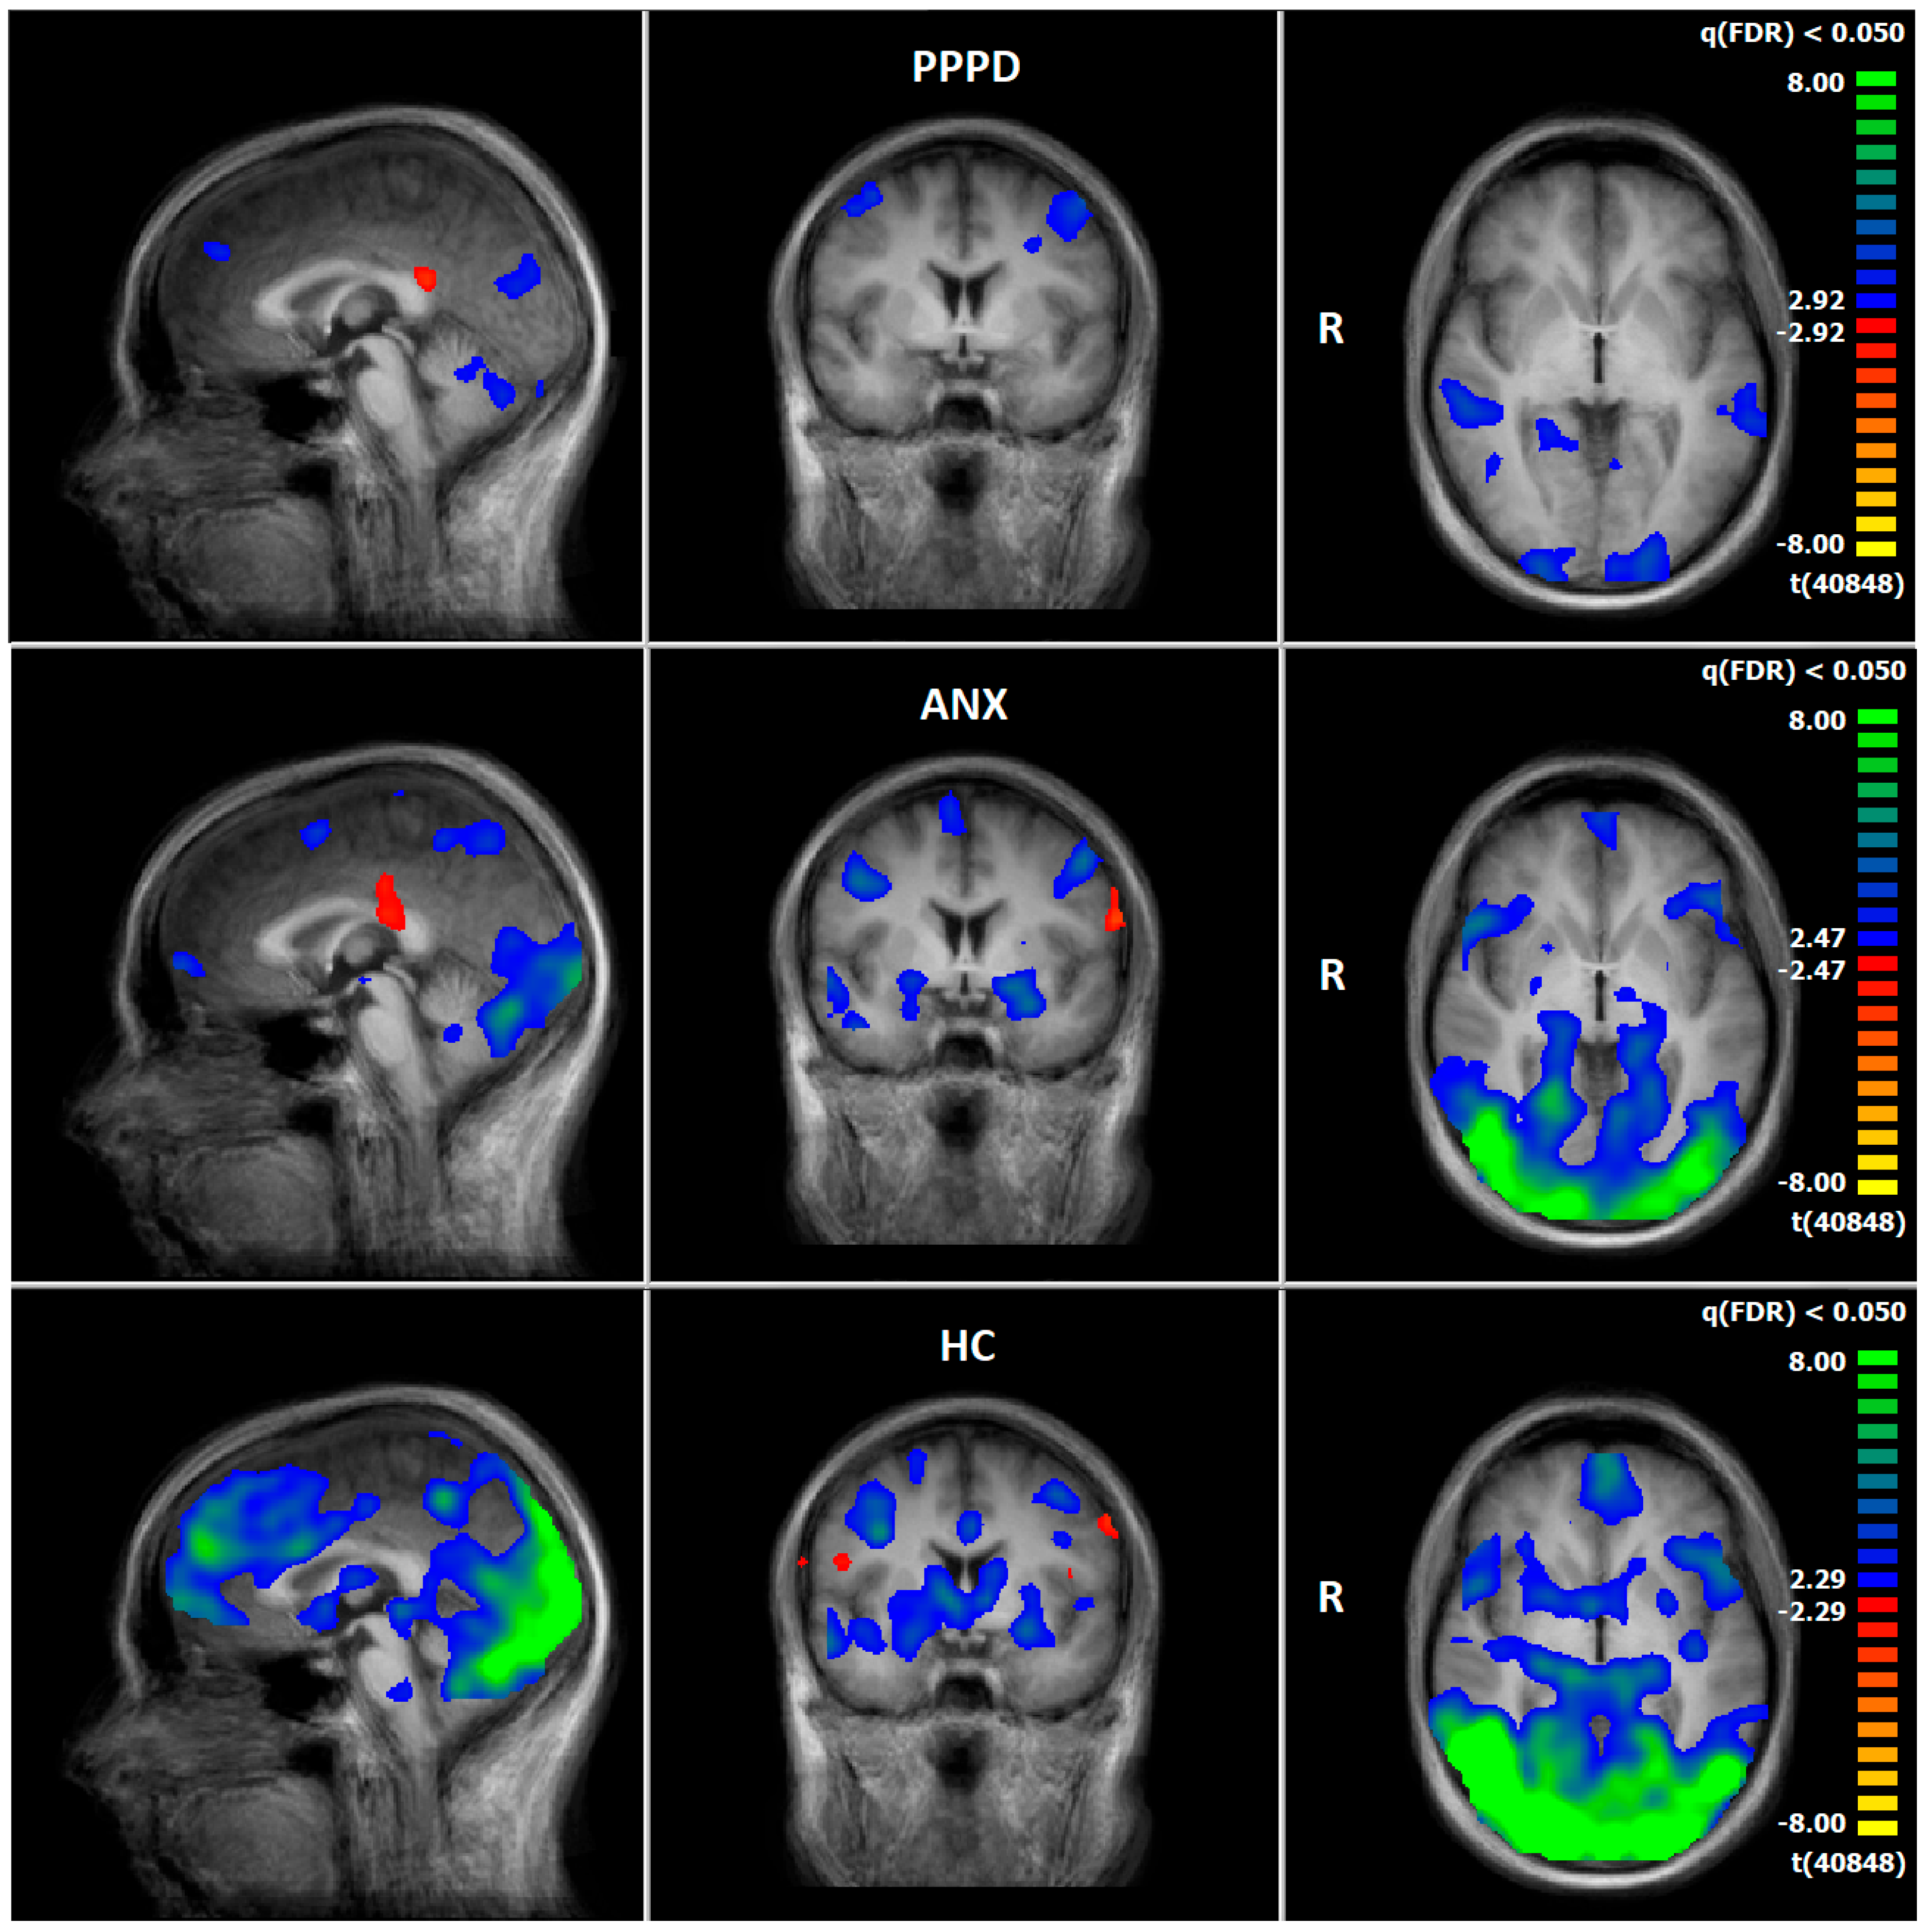

3.4. Comparison of Neuronal Responses Before and After Therapy—PPPD

3.5. Comparison of Neuronal Responses Before and After Therapy—ANX

3.6. HC: Pre–Post Comparison of Neuronal Responses Following a 5–6-Week Interval